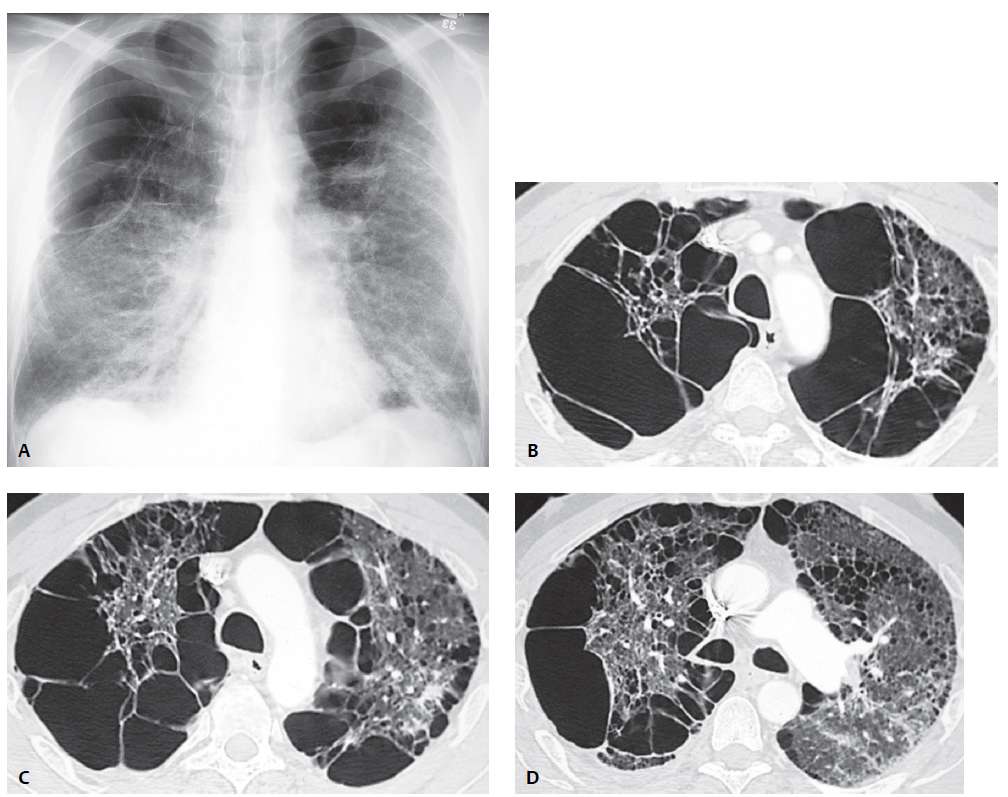

PA chest radiograph (A) demonstrates hyperinflation with bilateral upper lobe hyperlucency secondary to bilateral large apical bullae that compress adjacent lung. Bands of atelectasis are demonstrated at both lung bases.

High-resolution CT (lung window) (B, C, D) demonstrates bilateral large bullae that preferentially affect the right lung and produce mediastinal shift to the left. Scattered areas of proximal acinar emphysema and a single subpleural arcade of distal acinar emphysema are demonstrated in the left upper lobe (D).